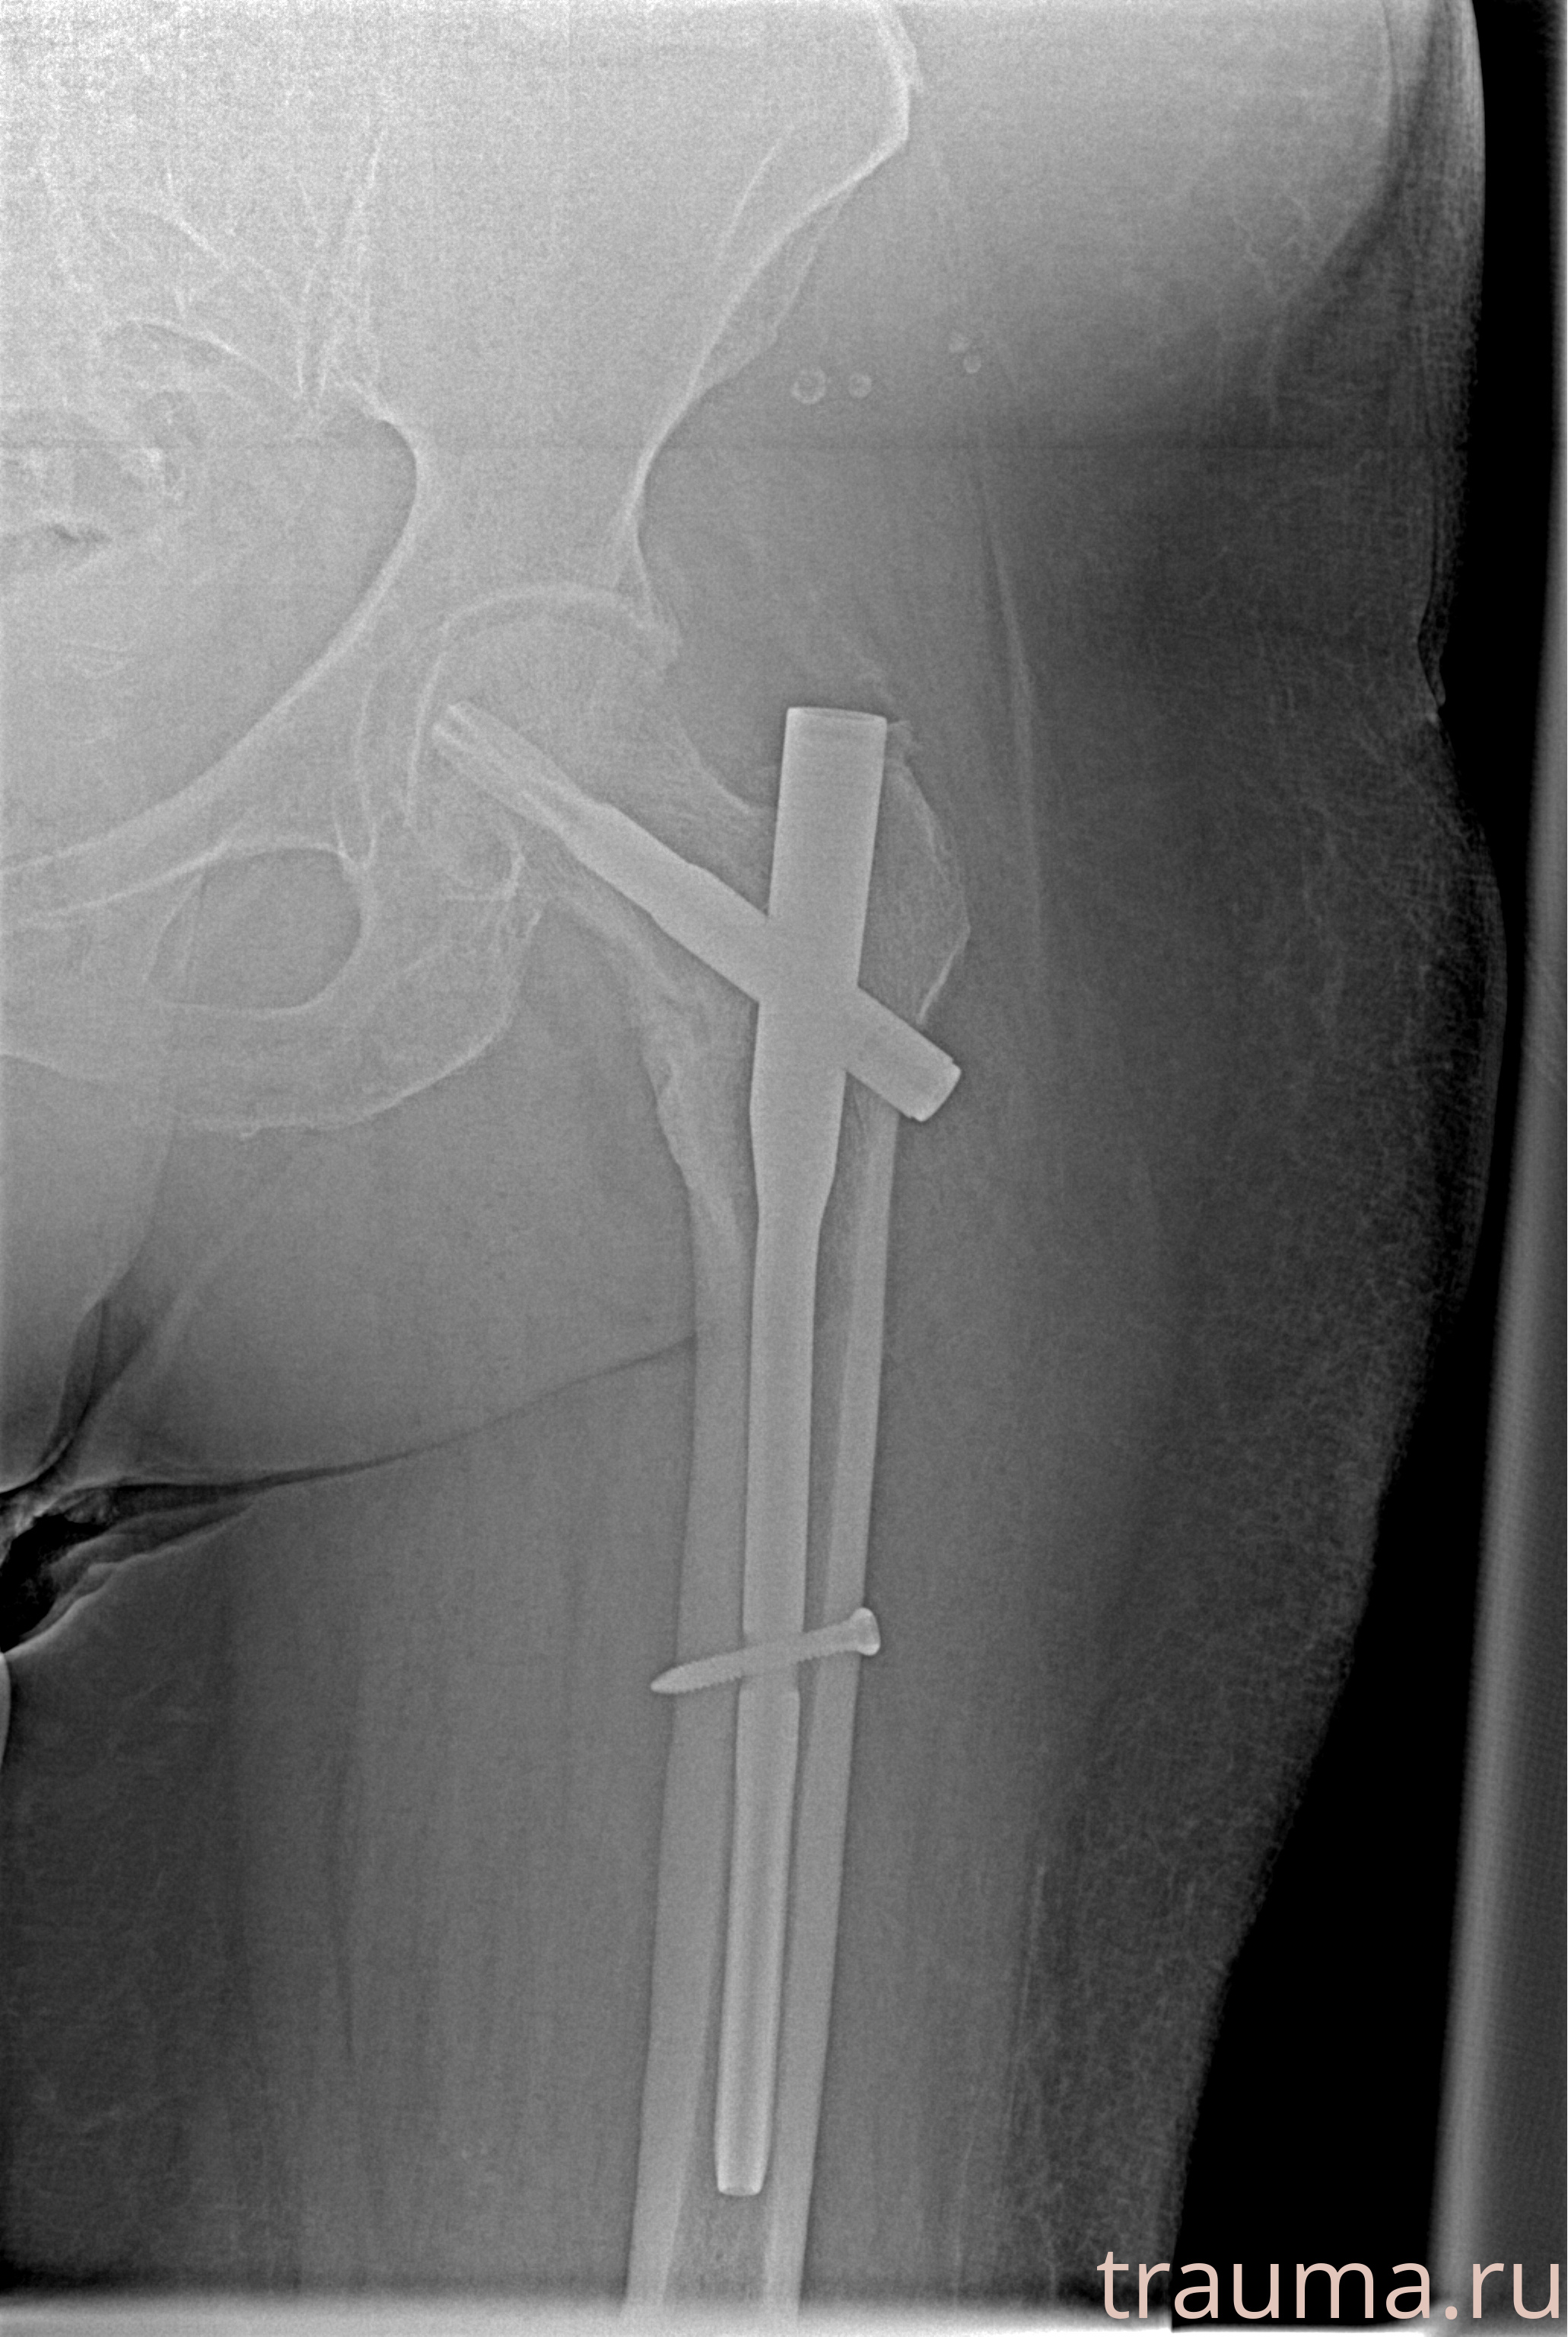

Рентгенограммы

Рентген на дому: по вашему адресу приезжает врач-рентгенолог, травматолог-ортопед с мобильным рентгеновским аппаратом, проводит диагностику травмы или заболевания, делает необходимые рентгенограммы, дает рекомендации по дальнейшему лечению. Получить качественные снимки в домашних условиях возможно благодаря уникальной методике, разработанной МосРентген Центром для института  Склифосовского